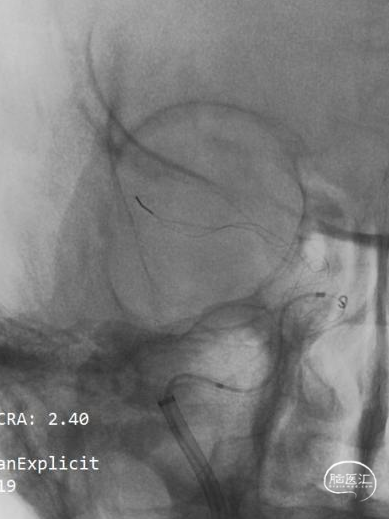

透视下可见Syphonet®取栓支架通体显影,有利于观察支架形态。

一次支架取栓后血管完全通畅,达到mTICI 3级。